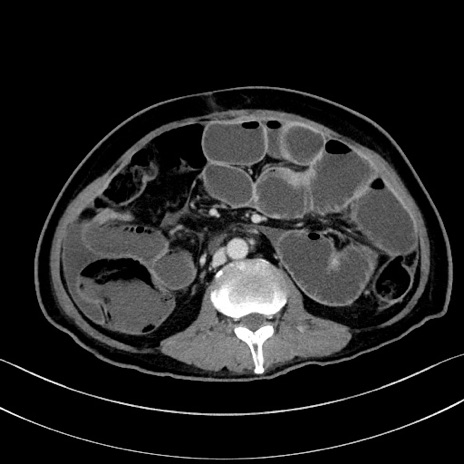

症例28(横断像)

【症例】60歳代男性

【主訴】嘔吐

【現病歴】胃癌にて胃全摘後。食思不振が悪化し、夜中に嘔吐することがある。

【既往歴】胃癌、胃全摘、脾摘、胆摘後

【データ】WBC 5900、CRP 10.56